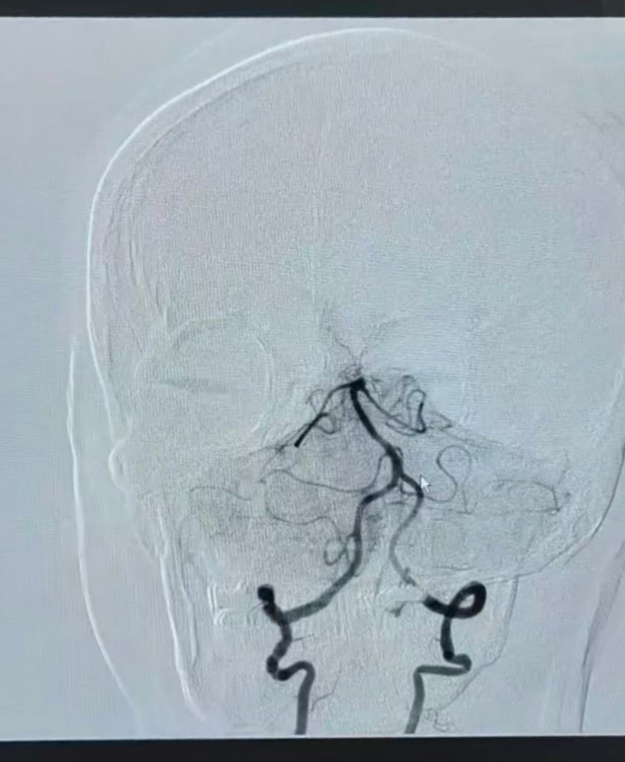

造影显示基底动脉再通

脑梗死急诊取栓通常耗时1-3小时。12分钟,刷新了医院此前25分钟的急诊取栓记录。当医生告诉家属血管已开通、手术顺利结束时。家属惊讶又喜悦:“这么快!还以为手术没开始呢。”